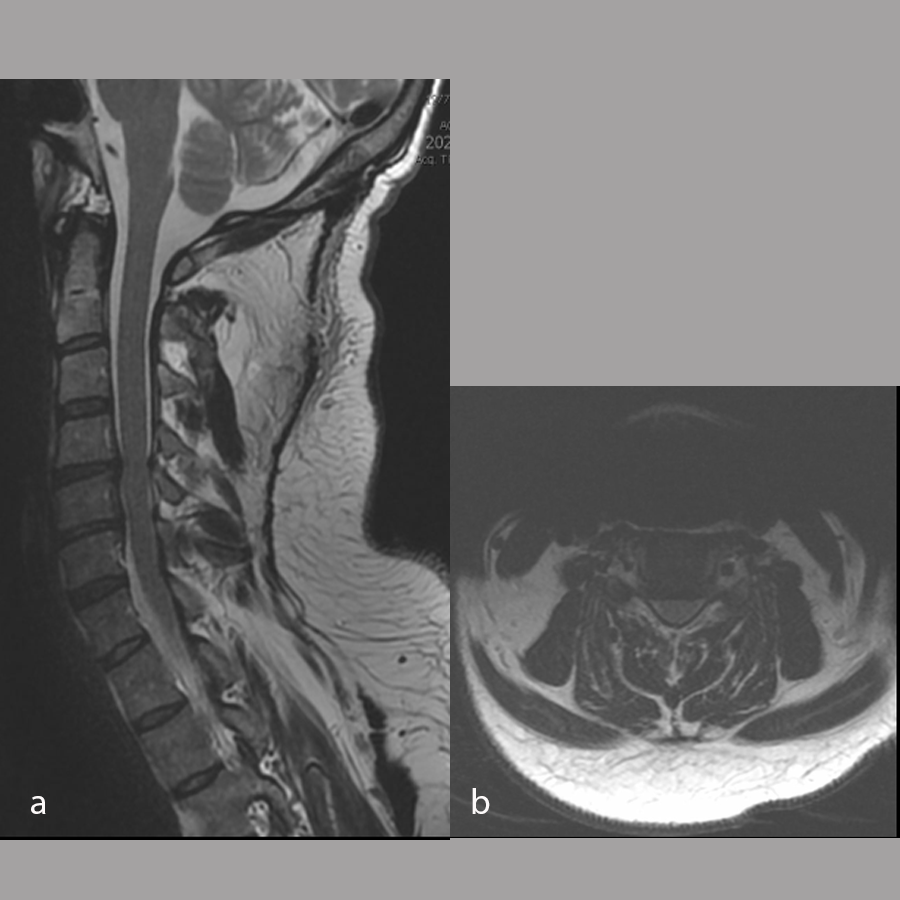

Magnetic resonance imaging of the cervical spine performed at the time of injury (Fig 8) was reviewed and showed:

- Spinal canal narrowing at C4/5 with cord compression and associated cord edema

- Bilateral uncovertebral osteophytes with mild bilateral foraminal narrowing

- C5/6 with mild posterior disc bulging causing mild canal narrowing without cord compression

- Mild bilateral foraminal narrowing of C6/7.

A diagnosis was made of cervical spinal stenosis largely attributable to stenosis at C4/5, with lesser stenosis at C5/6 and cord compression causing sub-acute central cord syndrome. Anterior decompression was recommended to alleviate symptoms, and C4/5 anterior cervical discectomy and fusion (ACDF) was performed on March 7, 2024. Fig 9 shows postoperative imaging.